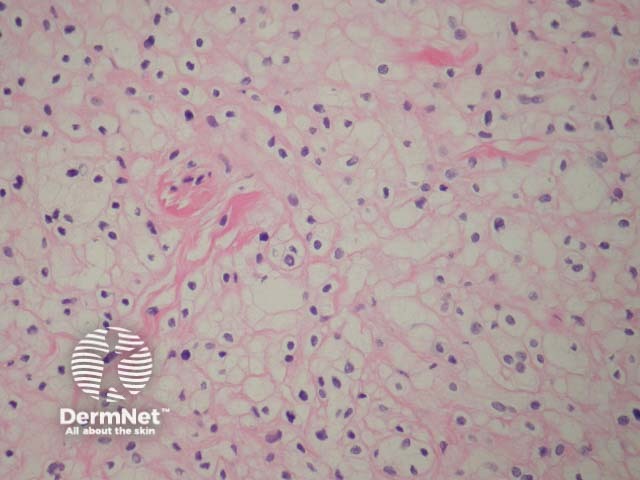

Intradermal naevi are dome-shaped, nodular or polypoid lesions that may become non-pigmented, particularly on the face. Nests of melanocytes are confined to the dermis. Melanocytes may show ‘pseudo-inclusions’, which are invaginations of cytoplasm into the nucleus giving the appearance of nuclear inclusions or cells with multiple nuclei. Deeper, the naevus cells may become spindle-shaped or ‘neurotised’. Fatty differentiation is not uncommon. Bone formation is a very rare finding in common naevi (naevus of Nanta) (figure 4).

Figure 4